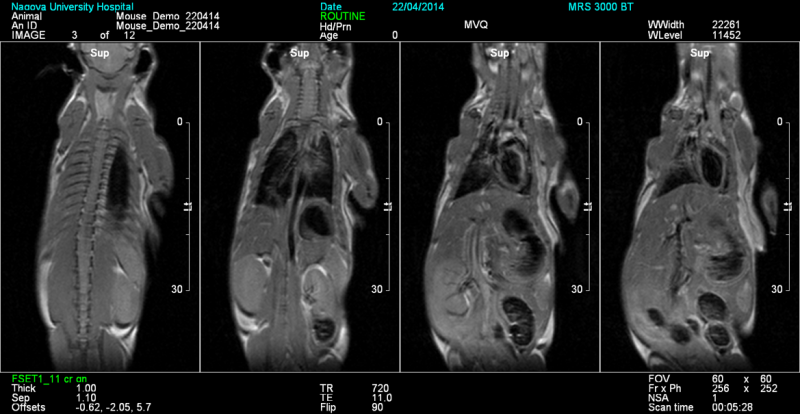

Безкриогенный МР-томограф 3.0Т, основанный на запатентованной технологии «сухих» магнитов: MRS*DRYMAG. МРТ-система специально разработана для молекулярной визуализации грызунов и крупных животных, применений in vivo и ex vivo.

- Превосходный контраст мягких тканей и молекулярная визуализация для диагностики и трансляционных исследований;

- Высокое пространственное разрешение для визуализации и количественного анализа;

Как и другие доклинические методы, МРТ может неинвазивно отслеживать биологические переменные in vivo и последовательно отслеживать прогрессирование заболевания или последствия вмешательства у животного, таким образом улучшая биологическую и трансляционную значимость исследования. МРТ не имеет аналогов в предоставлении подробных анатомических и морфологических данных для структур мягких тканей.